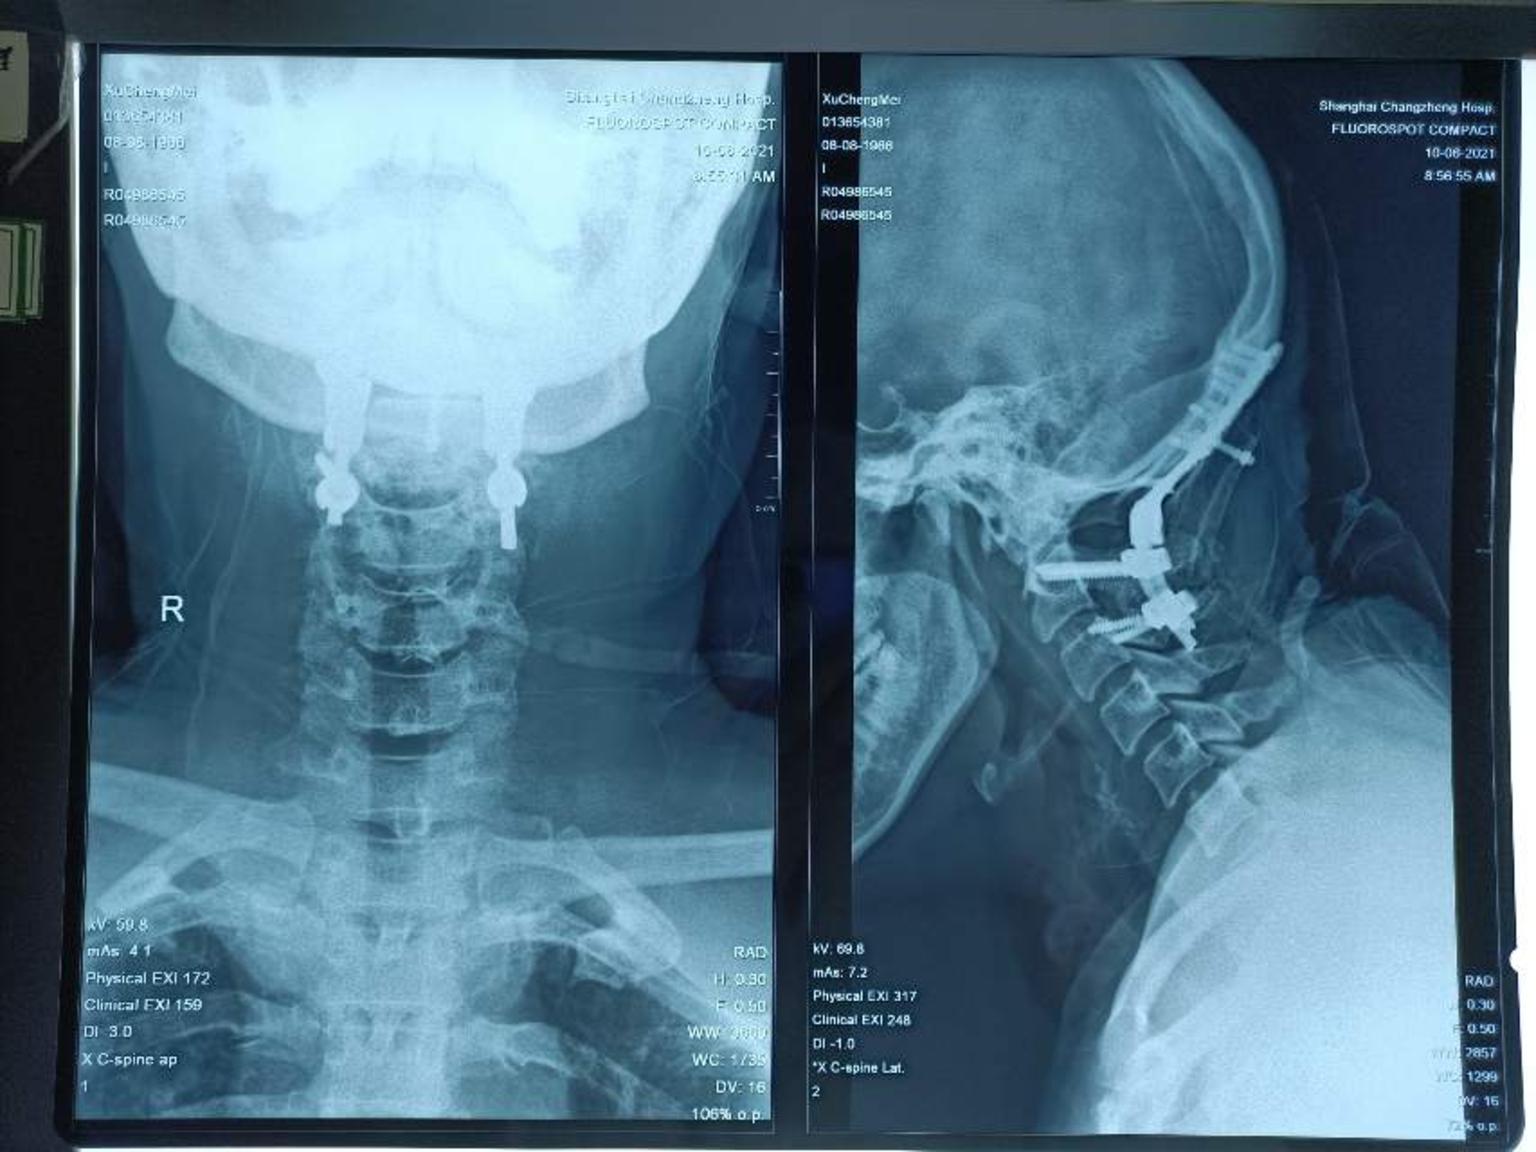

颅底凹陷症

罕见病例颅底凹陷先天性寰椎枕骨化